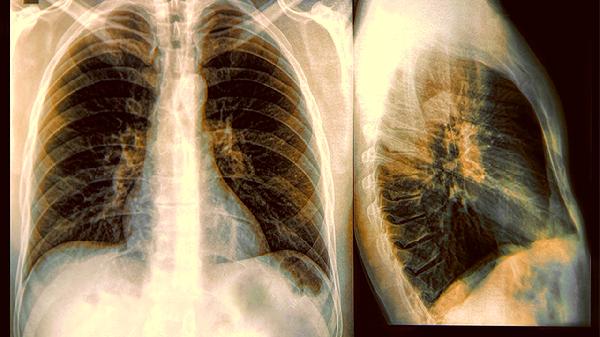

以为是骨质疏松,结果是肺癌!3种腿部表现,是你的肺在求救!